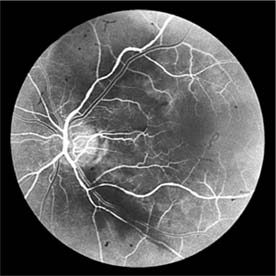

Figure 15-10

Figure 15-10: Accelerated hypertension. Fluorescein angiogram in a young man showing arteriolar constriction, dilation of capillaries with microaneurysms, and areas of closure. Marked disk edema is present.

In contrast, elderly patients with arteriosclerotic vessels are unable to respond in this manner, and their vessels are thus protected by the arteriosclerosis. It is for this reason that elderly patients seldom exhibit florid hypertensive retinopathy (Figure 15-11).

Figure 15-11

Figure 15-11: Accelerated hypertension. Fluorescein angiogram in an elderly wom.an showing marked arteriolar constriction and irregularity but few signs of florid retinopathy.

Fluorescein angiography has made possible accurate documentation of these microcirculatory changes. In young patients with hypertension, arteriolar attenuation and occlusion are seen, and capillary nonperfusion can be verified in relation to a cotton-wool spot, which is surrounded by abnormal dilated capillaries and microaneurysms with increased permeability on fluorescein angiography.